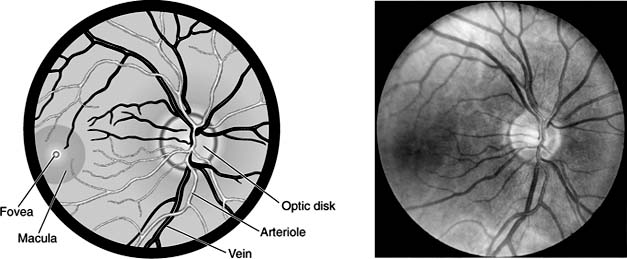

The primary value of the direct ophthalmoscope is in examination of the fundus (Figure 2-13). The view may be impaired by cloudy ocular media, such as a cataract, or by insufficient pupillary dilation. As the patient fixates on a distant target with the opposite eye, the examiner first brings retinal details into sharp focus. Since the retinal vessels all arise from the disk, the latter is located by following any major vascular branch back to this common origin. At this point, the ophthalmoscope beam will be aimed slightly nasal to the patient's line of vision, or "visual axis." One should study the shape, size, and color of the disk, the distinctness of its margins, and the size of the pale central "physiologic cup." The ratio of cup size to disk size is of diagnostic importance in glaucoma (Figures 2-14 and 2-15).

Figure 2-13

Figure 2-13: Photo and corresponding diagram of a normal fundus. Note that the retinal vessels all stop short of and do not cross the fovea. (Photo by Diane Beeston.)

The macular area (Figure 2-13) is located approximately two "disk diameters" temporal to the edge of the disk. A small pinpoint white reflection or "reflex" marks the central fovea. This is surrounded by a more darkly pigmented and poorly circumscribed area called the macula. The retinal vascular branches approach from all sides but stop short of the fovea. Thus, its location can be confirmed by the focal absence of retinal vessels or by asking the patient to stare directly into the light.

The major retinal vessels are then examined and followed as far distally as possible in each of the four quadrants (superior, inferior, temporal, and nasal). The veins are darker and wider than their paired arteries. The vessels are examined for color, tortuosity, and caliber as well as for associated abnormalities such as aneurysms, hemorrhages, or exudates. Sizes and distances within the fundus are often measured in "disk diameters (DD)." (The typical optic disk is generally 1.5-2 mm in diameter.) Thus, one might describe a "1 DD area of hemorrhage located 2.5 DD inferotemporal to the fovea."